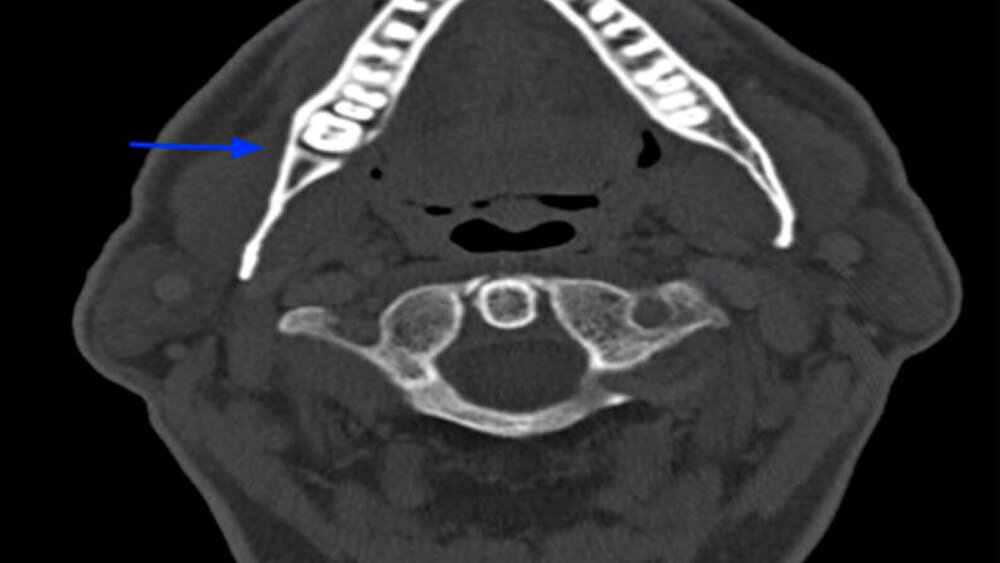

Anhand der klinischen Beurteilung wurde die Verdachtsdiagnose eines Plattenepithelkarzinoms gestellt. Differenzialdiagnostisch kam eine Epulis in Betracht. Zur Beurteilung der Befundausdehnung sowie zur Planung der weiteren Therapie wurde ein CT des Halses mit Kontrastmittel im Rahmen des Stagings durchgeführt. Im CT konnte das Ausmaß der Osteolysen ermittelt werden. Zu dem Zeitpunkt hatte keine Arrosion der Kortikalis stattgefunden (Abbildung 3). Darüber hinaus zeigten sich zahlreiche prominente und insbesondere rechtsseitig vergrößerte zervikale Lymphknoten, welche als metastasenverdächtig eingestuft wurden (Abbildung 4). Aufgrund der unklaren Dignität des Befundes erfolgte zur histologischen Diagnosesicherung die ambulante Probeentnahme in regio 048.